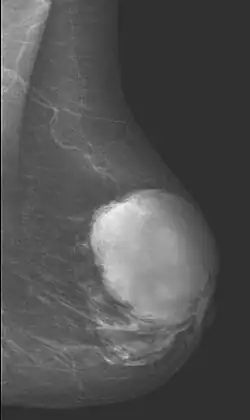

Phyllodes tumor in mammography

Radiographical imaging is the first-line test for identifying a phyllodes tumor.[11] Despite their propensity to grow rapidly and deform the overlying breast tissue, approximately 20% of phyllodes tumors can present as a nonpalpable mass on screening mammography.[12] Other imaging tools used to assess the size and spread of a phyllodes tumor include ultrasound and magnetic resonance imaging (MRI).[11] None of these imaging tools are definitive tests for differentiating a phyllodes tumor from a benign fibroadenoma.[13] Phyllodes tumors can only be diagnosed histologically, as they tend to have many overlapping features with other breast masses on physical examination and radiological imaging.[11]